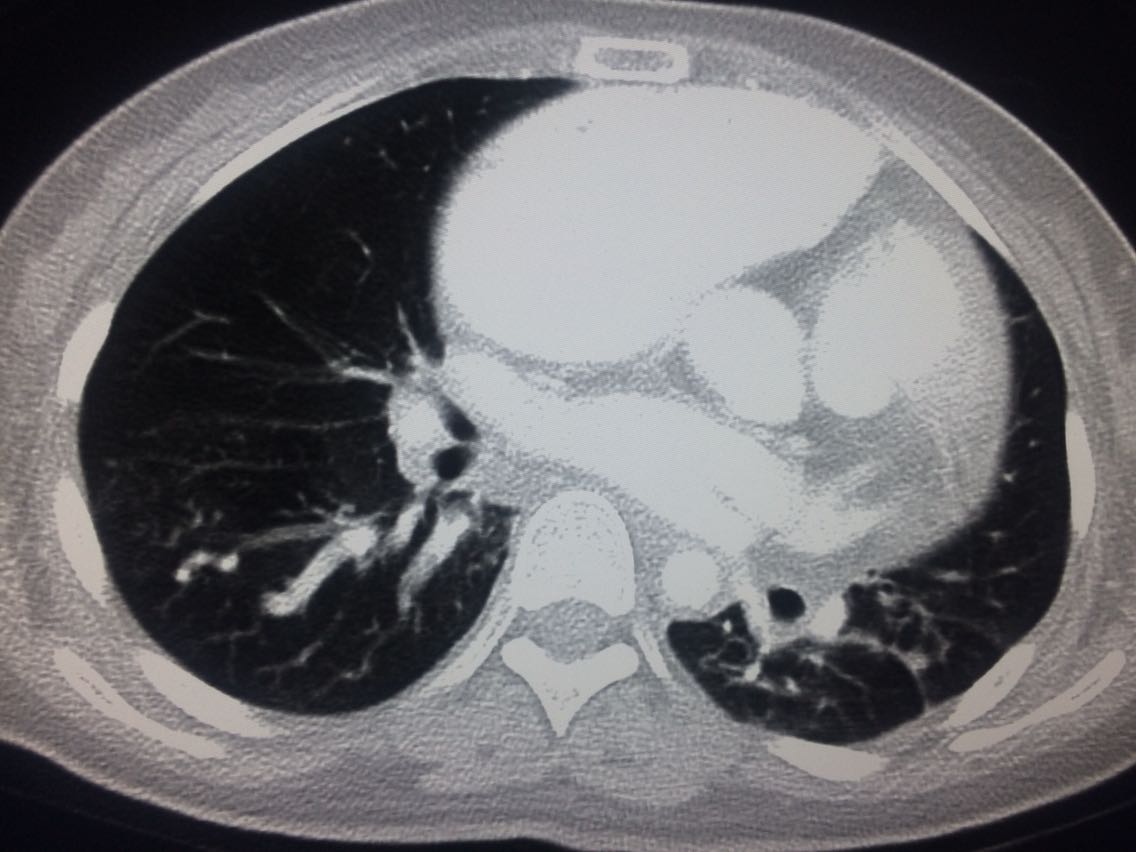

诊断,肺动脉高压。 鉴别诊断,肺动脉栓塞。 影像诊断,肺动脉高压,肺门区出现残根征,肺动脉扩张,肺动脉段膨隆,心影增大。CTA见迂曲增宽的肺动脉。 肺栓塞,影像可见典型充型缺损影,伴随肺纹理的减少。 治疗以对症处理为主,病人病史14年。 讨论诊断和鉴别诊断? 随访,症状好转。